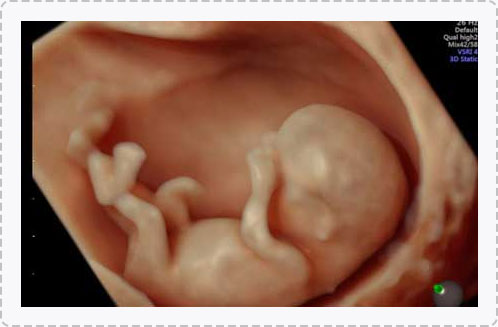

四维彩超能排查遗传性综合征等胎儿早期疾病。多角度观察宫内胎儿的生长发育情况,为早期诊断胎儿先天性体表畸形先天性心脏疾病提供科学依据。

四维彩超能够直观、立体地显示人体器官的三维结构以及动态,实时地观察立体结构,被广泛用于检查胎儿发育状况,立体观察胎儿在子宫内发育情况的同时,还能够清晰显示胎儿在子宫内的动态,让准爸妈们一起观看宝宝在妈妈肚子里的动作、神态,还可将这个过程制作成光碟保存,让宝宝能够拥有完整的0岁相册,留下珍贵的纪念。

四维彩超检查能够多角度观察胎儿在子宫内的发育状况,同时能够为早期诊断胎儿先天性体表畸形、先天性心脏疾病提供准确的科学依据。